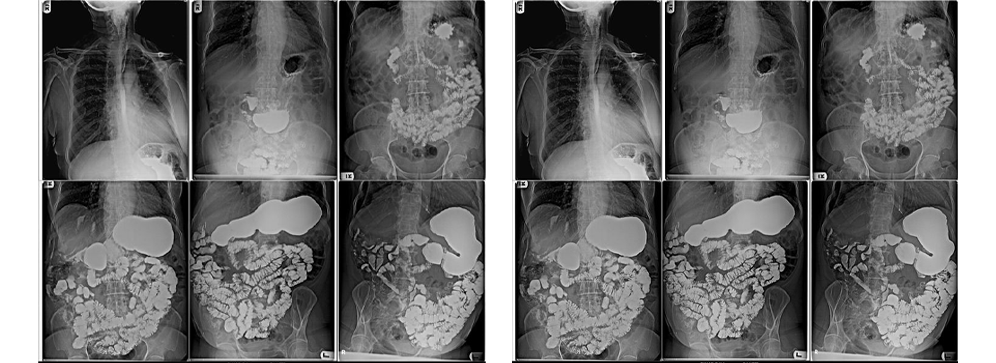

At Insight Diagnostics and Labs, we recognize that accurate diagnosis of digestive tract disorders plays a crucial role in delivering effective treatment and improving patients' quality of life. The Barium Meal Follow Through (BMFT) is a vital diagnostic imaging procedure designed to provide a detailed and dynamic visualization of the upper gastrointestinal tract, including the stomach and small intestine. This procedure involves the patient ingesting a barium sulfate contrast medium, which coats the lining of the digestive tract, allowing radiologists to track its passage using a series of X-ray images over time. The dynamic nature of BMFT offers a unique advantage by not only showing the anatomy but also assessing the motility and function of the digestive system.

A Barium Meal Follow Through (BMFT) is a detailed radiological examination that evaluates the anatomy and functionality of the stomach and small intestine. After swallowing a specially prepared barium sulfate suspension—a chalky, radiopaque contrast agent—the patient undergoes sequential X-rays taken at intervals to observe how the barium moves through the gastrointestinal tract. This real-time tracking helps identify a wide range of abnormalities such as ulcers, strictures (narrowing), tumors, areas of inflammation, and motility disorders that affect how food passes through the intestines.

At Insight Diagnostics and Labs, the BMFT is conducted using advanced digital radiography, a technology that offers continuous, live imaging with exceptional clarity. This method allows our radiologists to monitor both the shape and function of the digestive tract during the entire transit of barium. Unlike static images, this dynamic study can reveal subtle abnormalities that might otherwise be missed, providing a comprehensive picture of your digestive health. Our highly skilled radiologists analyze these images to detect even the smallest signs of disease or dysfunction, assisting your doctor in planning effective treatments.

The BMFT procedure begins with the patient drinking a barium sulfate contrast medium, which is typically a chalky white liquid with a mild taste. This contrast coats the lining of the stomach and intestines, making them visible on X-rays. Once ingested, the patient lies on the X-ray table, and a series of X-ray images are taken at regular intervals over one to three hours. Digital radiography allows continuous, live imaging, enabling the radiologist to track the barium’s progression and observe how the stomach and small bowel move and contract.